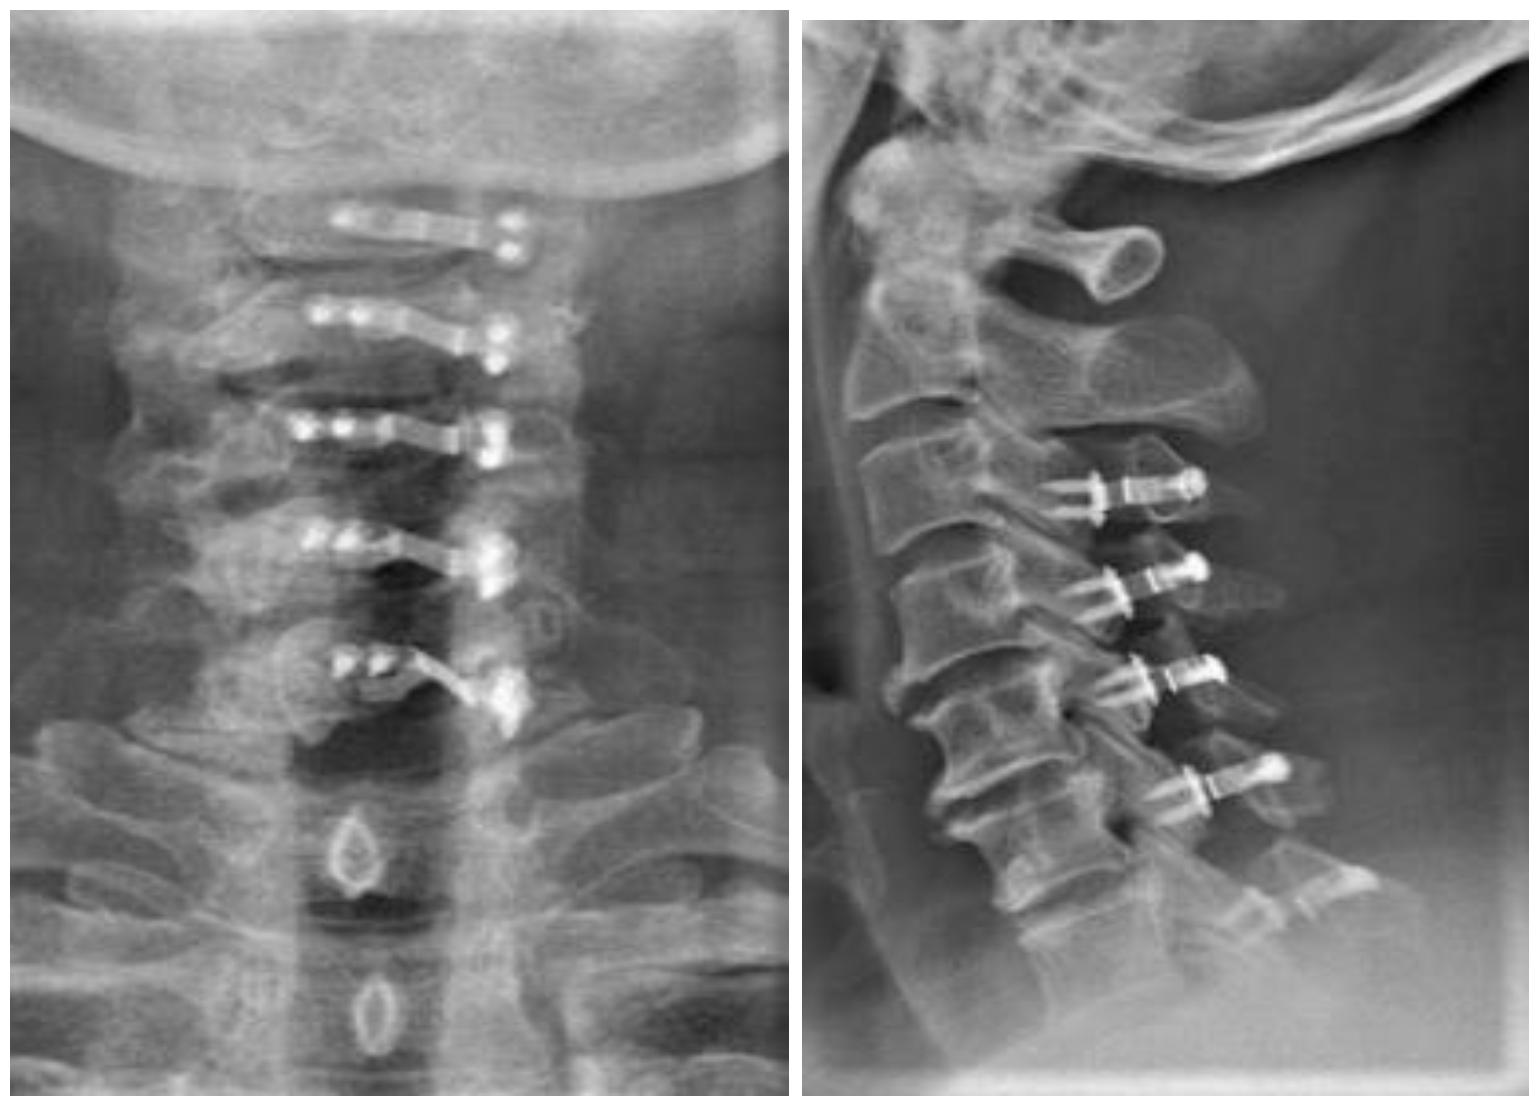

椎板成形术 (单开门颈椎管扩大成形术)